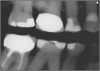

Excellent diagnosis essentially begins with two fundamental components: a doctor willing to listen to the patient’s chief complaint, and proper diagnostic tools. Among the most important tools are a precise periapical radiograph (PA) and bitewing (BW). Although a PA is often enough to provide an accurate portrayal of the patient’s condition, sometimes it alone does not suffice. Figure 1, Figure 2, and Figure 3 demonstrate a case that illustrates this point clearly. Despite two acceptable PAs (Figure 1 and Figure 2), it is difficult to assess the source of the patient’s pain to temperature. However, the BW radiograph Figure 3 provides significantly more clarity than either of the two PAs. The BW depicts localized bone loss (around tooth No. 2), a pulp stone (No. 2), a flat occlusion, numerous calcified canals, multiple restorations in tooth No. 30, and gross decay especially on tooth No. 3, which is the source of the patient’s pain to temperature. In this instance these images depict how much more useful a BW can be than just a conventional PA.

Fig 3. BW of the same upper right area as shown in Figure 1 and Figure 2, depicting gross decay not visualized on prior PAs.

Figure 3